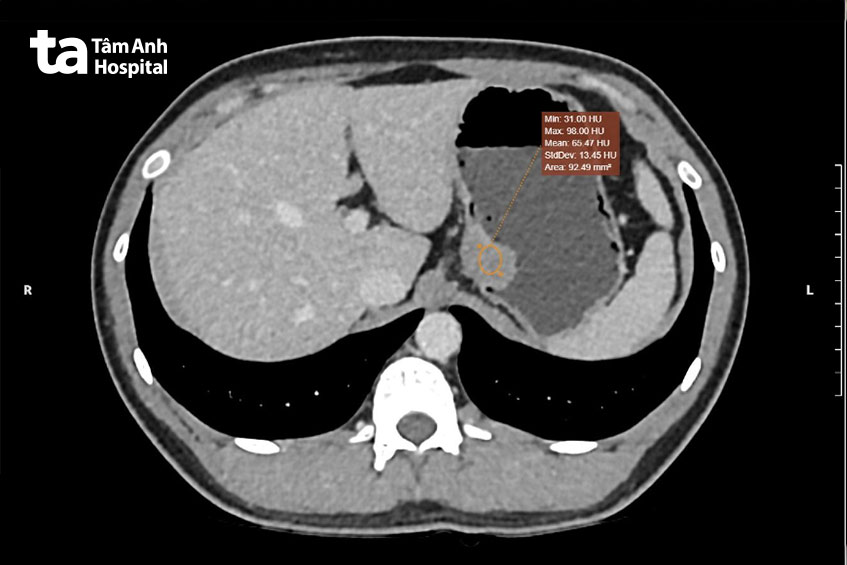

Ngày 22/8, bác sĩ chuyên khoa 2 Nguyễn Quốc Thái, Trung tâm Nội soi và Phẫu thuật Nội soi Tiêu hóa, Bệnh viện Đa khoa Tâm Anh TP HCM cho biết, kết quả chụp cắt lớp vi tính bụng (CT) có khối u kích thước 21 x 30 x 27 mm ở tâm vị (vị trí ở cuối thực quản và đầu dạ dày) chưa xâm lấn mô xung quanh, chưa xuất hiện hạch. Nội soi dạ dày cũng ghi nhận người bệnh bị viêm dạ dày và trào ngược dạ dày – thực quản.

Tuy nhiên, do khối u nằm dưới lớp niêm mạc tâm vị, ở mặt sau dạ dày nên không thể tiến hành sinh thiết khối u trong lúc nội soi. Vì thế chưa xác định được bản chất của khối u. U lại nằm ở vị trí khuất nên không thể can thiệp trong lúc nội soi. Tuy nhiên, cần phải phẫu thuật lấy khối u càng sớm càng tốt, tránh để khối u phát triển bít lòng thực quản. Hoặc nếu u ác tính, các tế bào ung thư có thể xâm lấn sang các cơ quan lân cận.